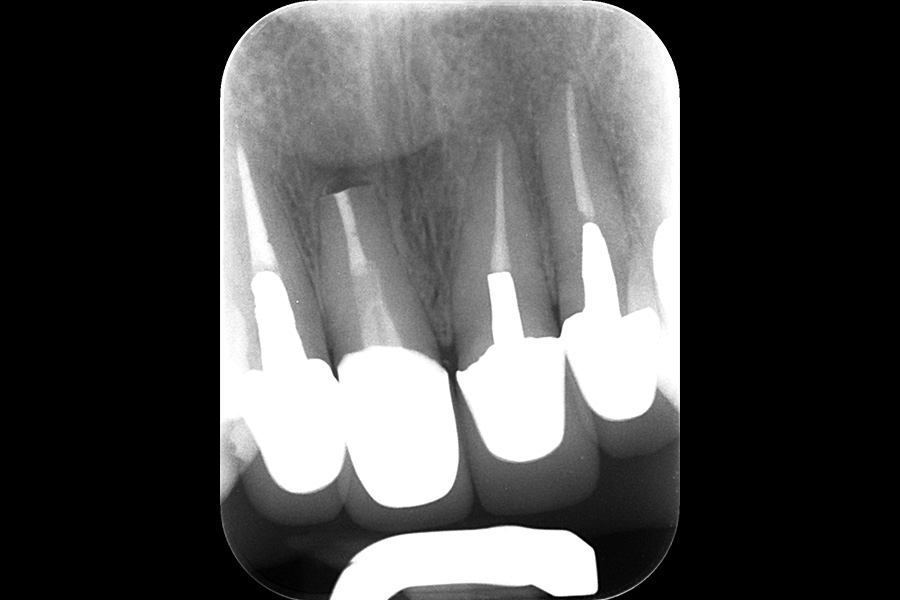

治療後